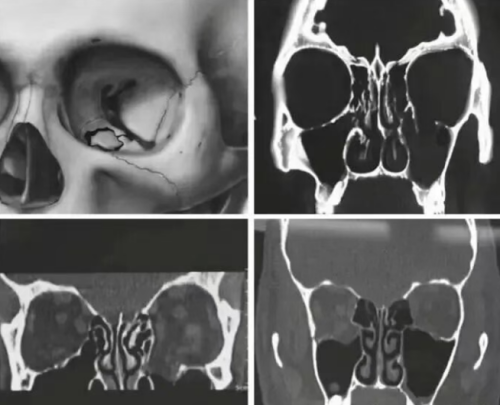

The Application of Titanium Alloys in Orbital Fracture Repair: Opportunities and Challenges